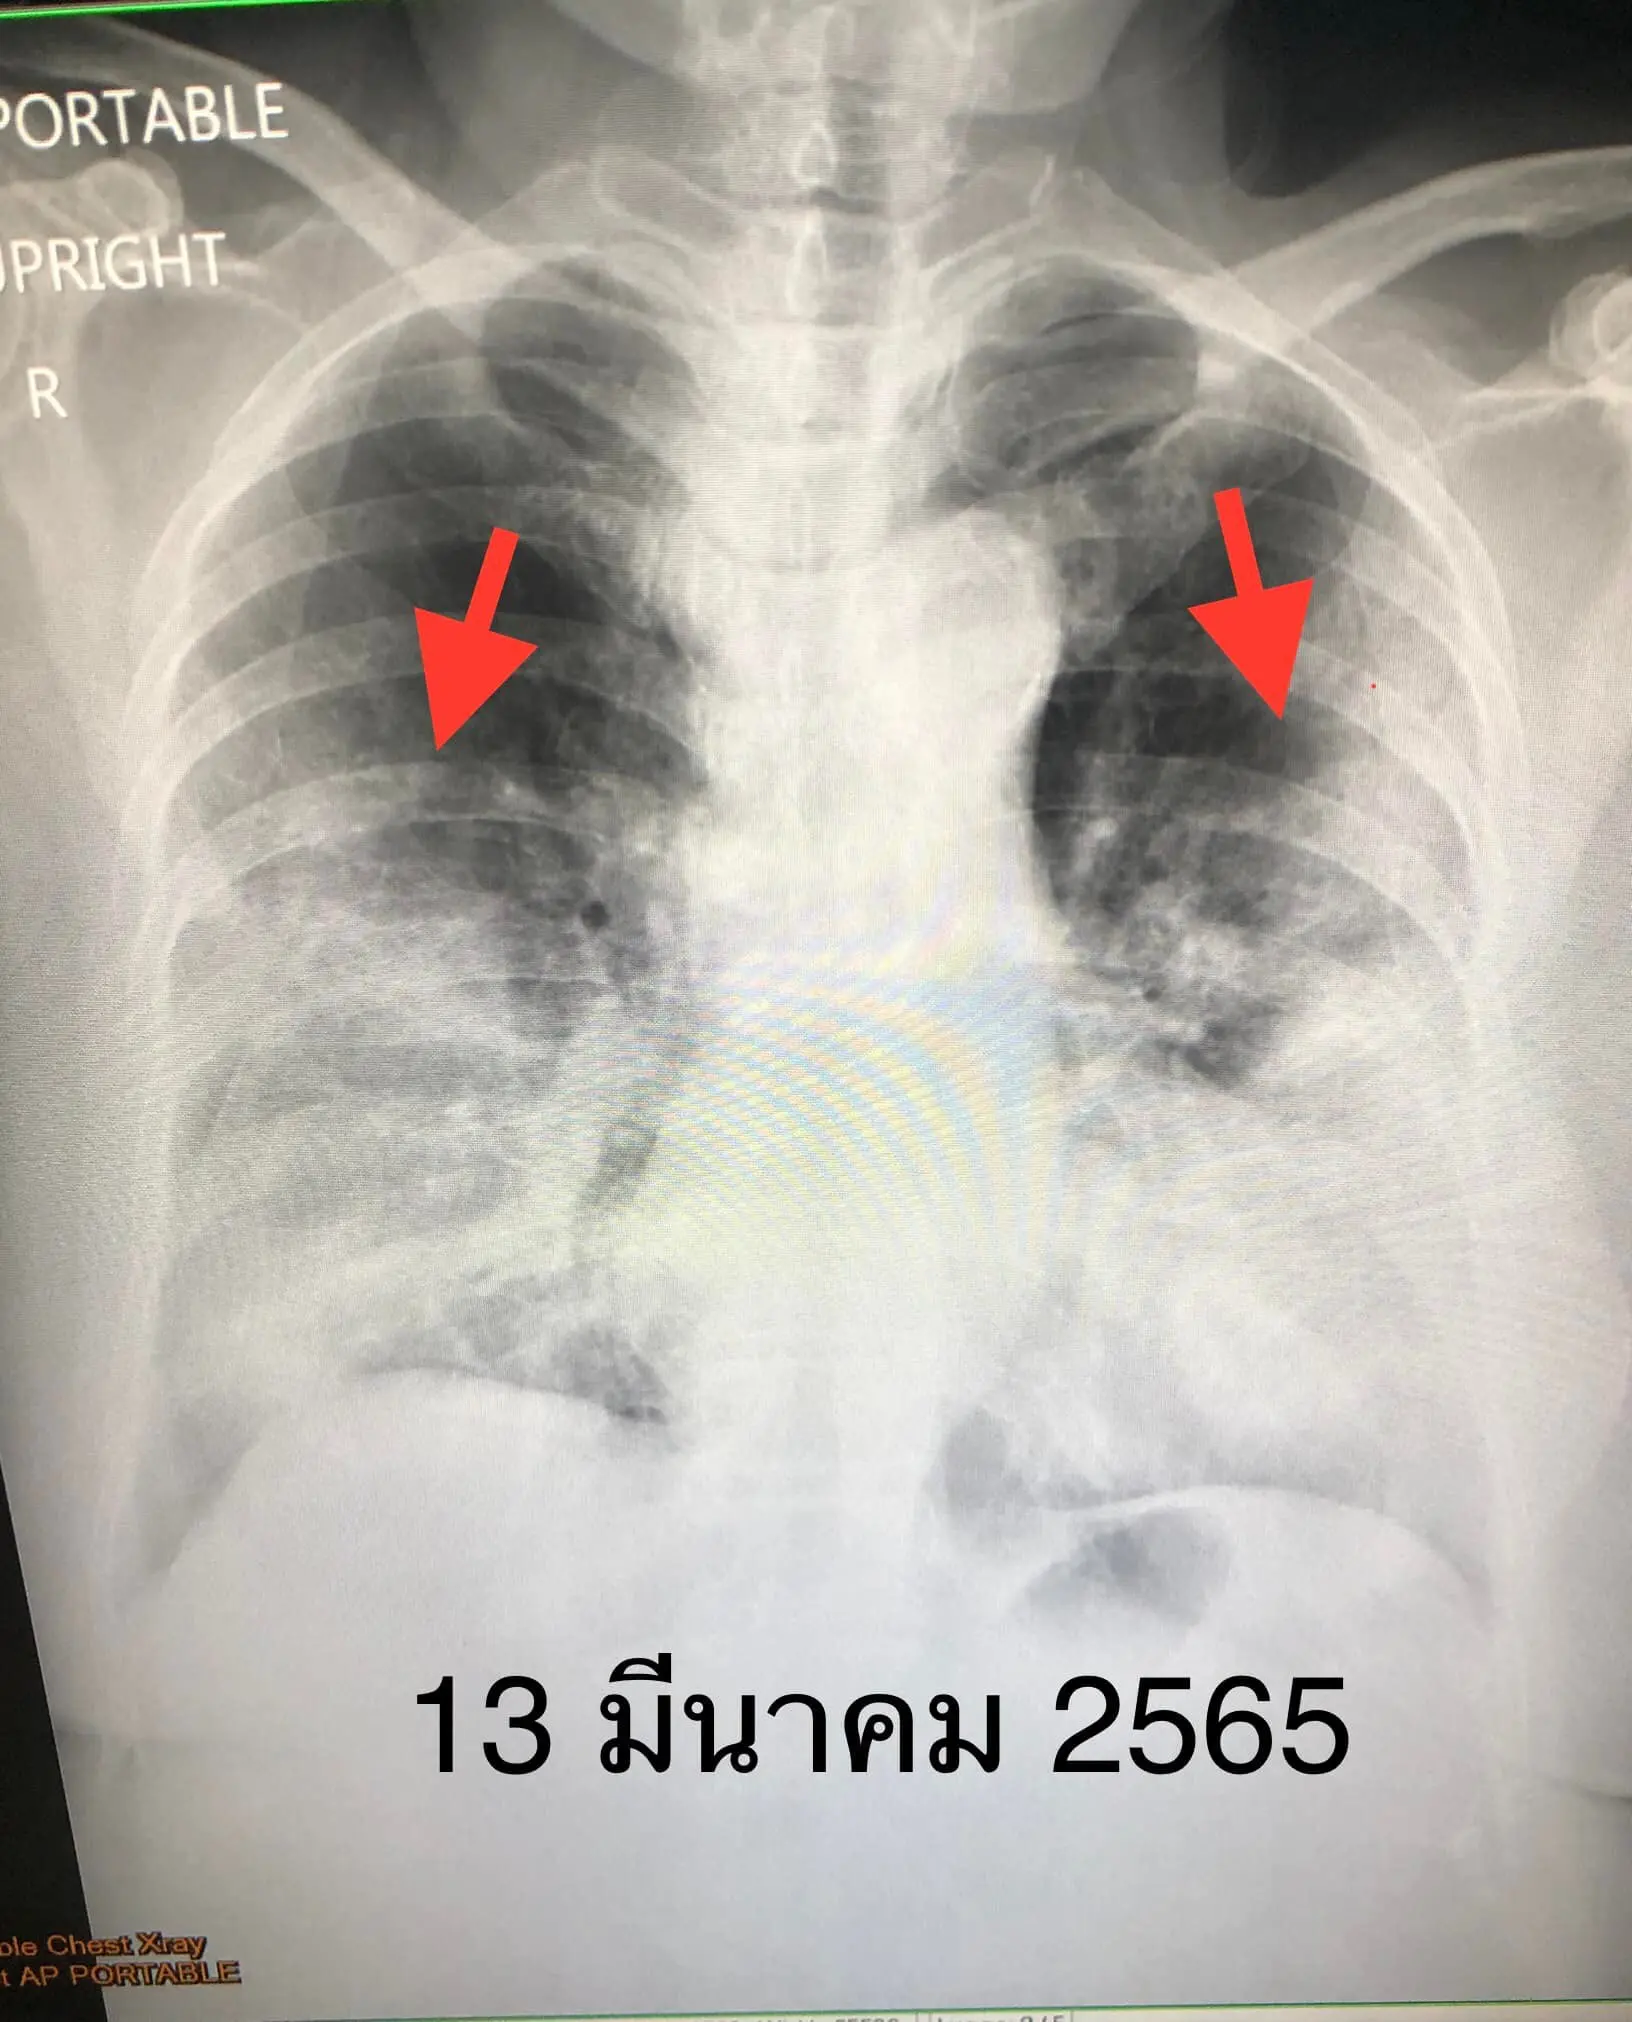

เข้านอนใน รพ.วันที่ 5-9 มีนาคม ระหว่างอยู่รพ. 5 วัน ไม่เหนื่อย ไม่มีไข้ วัดระดับออกซิเจนปกติ เอกซเรย์ปอดปกติ อนุญาตให้กลับบ้าน หลังกลับบ้าน 2 วัน เริ่มมีเหนื่อย หายใจลำบาก แน่นหน้าอก ไม่มีไข้ วัดระดับออกซิเจนเหลือ 92% เรียกรถฉุกเฉินมาส่งโรงพยาบาลวันที่ 12 มีนาคม เอกซเรย์ปอดมีฝ้าขาวทั้ง 2 ข้างเข้าได้กับปอดอักเสบจากการติดเชื้อไวรัสโควิด-19 (ดูรูป) ได้ให้ยาสเตียรอยด์ และยาเรมเดซิเวียร์ชนิดฉีด คนไข้ดีขึ้นเร็วใน 5 วัน